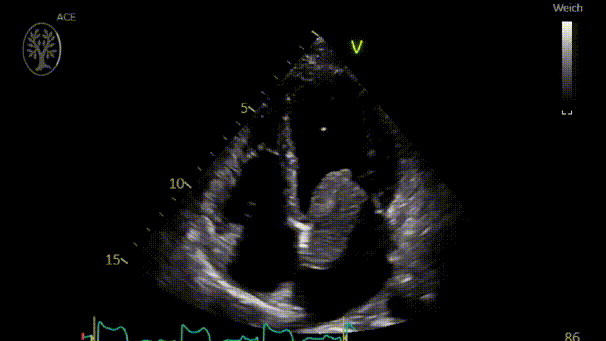

患者入院时血压正常(114/65mmHg),心律规整(76次/分钟),心脏听诊无杂音,无心力衰竭迹象和局灶性神经功能缺损。双侧股动脉和桡动脉搏动可触及,但双侧胫后动脉和足背动脉搏动消失。踝肱比(ABI)右侧为0.9,左侧为0.8。心电图示P波双相,经胸超声心动图显示LVEF正常,无室壁运动异常,左心房内有一个较大占位(5.1×2.5×2.8cm),通过二尖瓣进入左心室,导致中度二尖瓣狭窄(视频1,视频2)。

胸部CT示左心房内有蒂肿块,通过二尖瓣突出到左心室(图1)。下肢超声显示双侧腘动脉血栓形成,但双侧肢体仍通过侧支循环保持灌注。

图1.CT示左心房内有蒂肿块